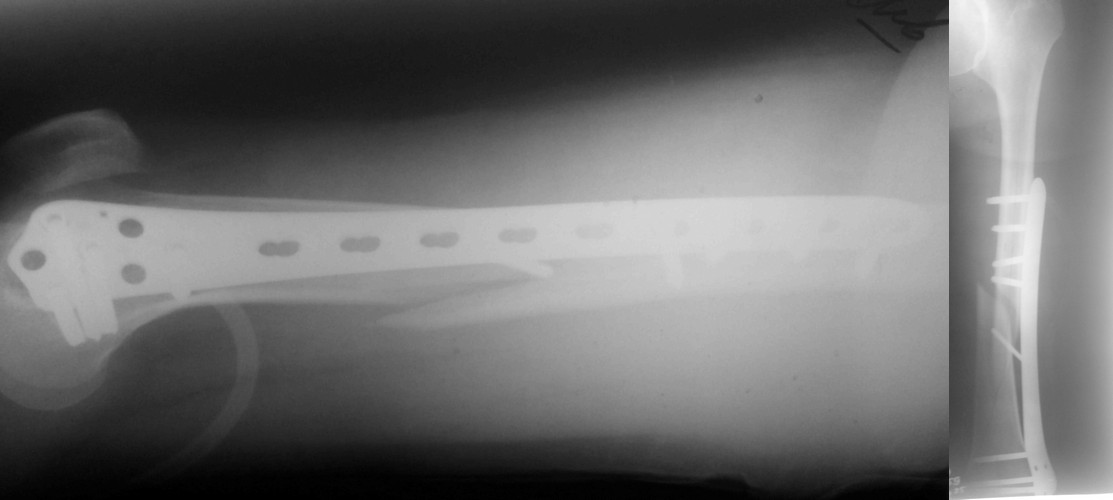

Представляю вам один из наших недавних случаев выполнения малоинвазивного остеосинтеза бедренной кости обычной пластиной 95 градусов. Длина восстановлена с помощью дистрактора (по сути это основная и б(о)льшая часть репозиции). Произведено два небольших доступа, проведена спица направитель. Рентген-контроль для подтверждения достаточной длины/оси (ЭОП использовался в другой операционной). Создание туннеля обратной стороной фиксатора. Поворот фиксатора, введение клинка по спице. Фиксация проксимального и дистального концов пластины.

Получилось очень симпатично, поздравляю и восхищаюсь мастерством.

Хотя закрытый остеосинтез блокированным гвоздем выглядит технически проще, особенно при диафизарных переломах. Не говоря о биомеханических преимуществах внутрикостного имплантата, еще меньшей инвазивности, возможности динамизации при проблемах со сращением... Стоимость гвоздей и пластин сопоставимая, на рынке есть масса отечественных предложений.

В приложении - недавний перипротезный перелом.